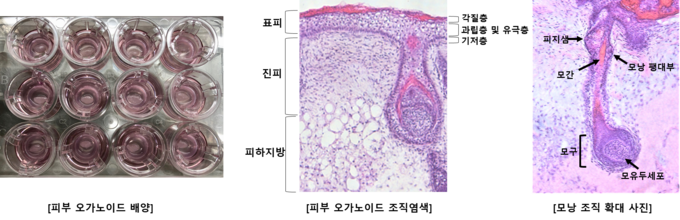

특히 가장 정확하지만 현실적으로 불가능했던 인체피부 채취를 통한 분석을 대신해 피부 오가노이드로 배양한 피부조직을 활용함으로써 기존의 한계를 극복했다. 피부조직 변화와 세포 내에서 진행되는 유전자, 단백질 발현 등을 직접 확인할 수 있게 돼 미용기기의 작용기전과 효과에 대한 정밀한 분석이 가능해진 것이다.

또 기존 피부 오가노이드 모델은 배양액에 완전히 잠겨있거나 표피층과 진피층이 뒤집혀 있는 낭포(cyst) 형태로 표피층에 직접 접촉하는 평가가 불가능했다.

그러나 (주)강스템바이오텍의 피부 오가노이드는 공기-액체 계면 배양방식을 도입해 표피층은 공기 중에, 진피층은 배양액에 노출시켜 실제 피부와 유사한 환경을 재현했다. 이에 표피층에 직접 접촉이 가능할 뿐 아니라 다양한 크기의 미용기기에 대한 평가가 가능해졌다.